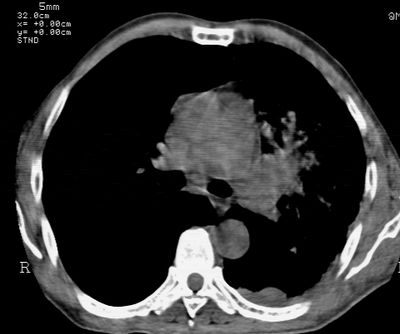

标题: CT24000:M65,胸痛,胸闷月余,既往慢支,肺气肿,肺心病 [打印本页]

标题: CT24000:M65,胸痛,胸闷月余,既往慢支,肺气肿,肺心病

左肺门肿块,相应支气管闭塞,左肺上叶、舌叶大片及散在高密度影,部分呈不张改变,两肺纹粗乱,左侧胸腔积液。考虑左侧中央型肺癌伴阻塞性改变。

左肺门见巨大软组织肿块影,直径约--,境界清,左上肺叶支气管变窄,左上肺舌叶见大片状密实影,余肺纹理增多、紊乱、纤细、部分网格状,两肺透亮度增高,纵隔内见增大多发淋巴结影,心影略左偏,左侧少量胸腔积液。

左侧中央型肺癌伴左上肺舌叶不张、纵隔淋巴结转移,左侧少量胸腔积液。